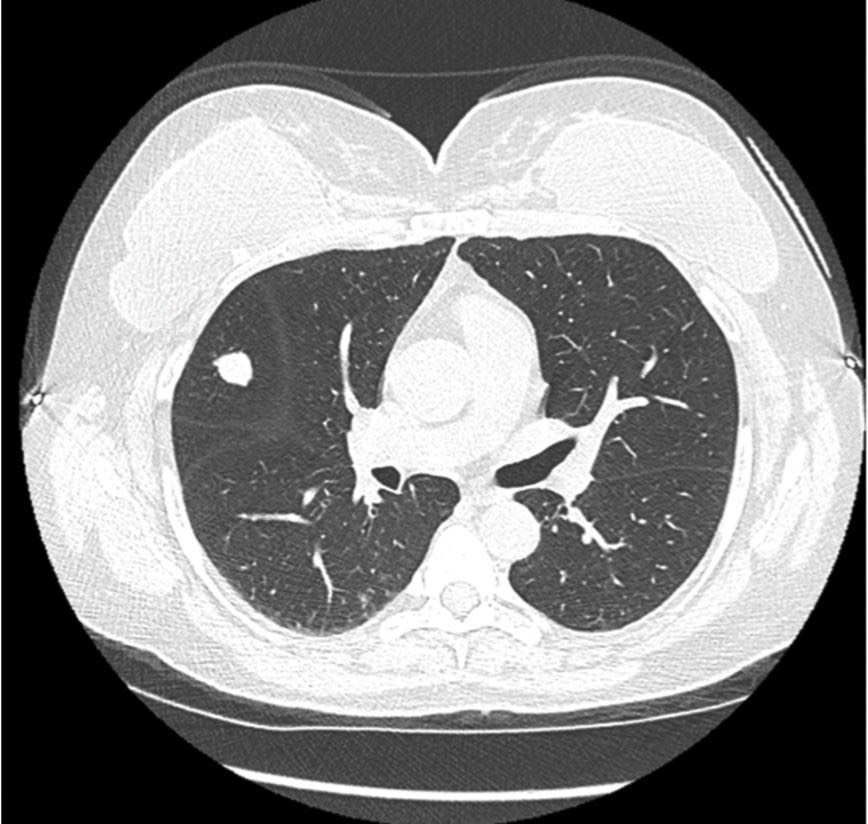

1361. Учитывая представленную на компьютерном срезе локализацию malt-лимфомы, оптимальным объёмом оперативного вмешательства является ______________ с удалением регионарных лимфоузлов